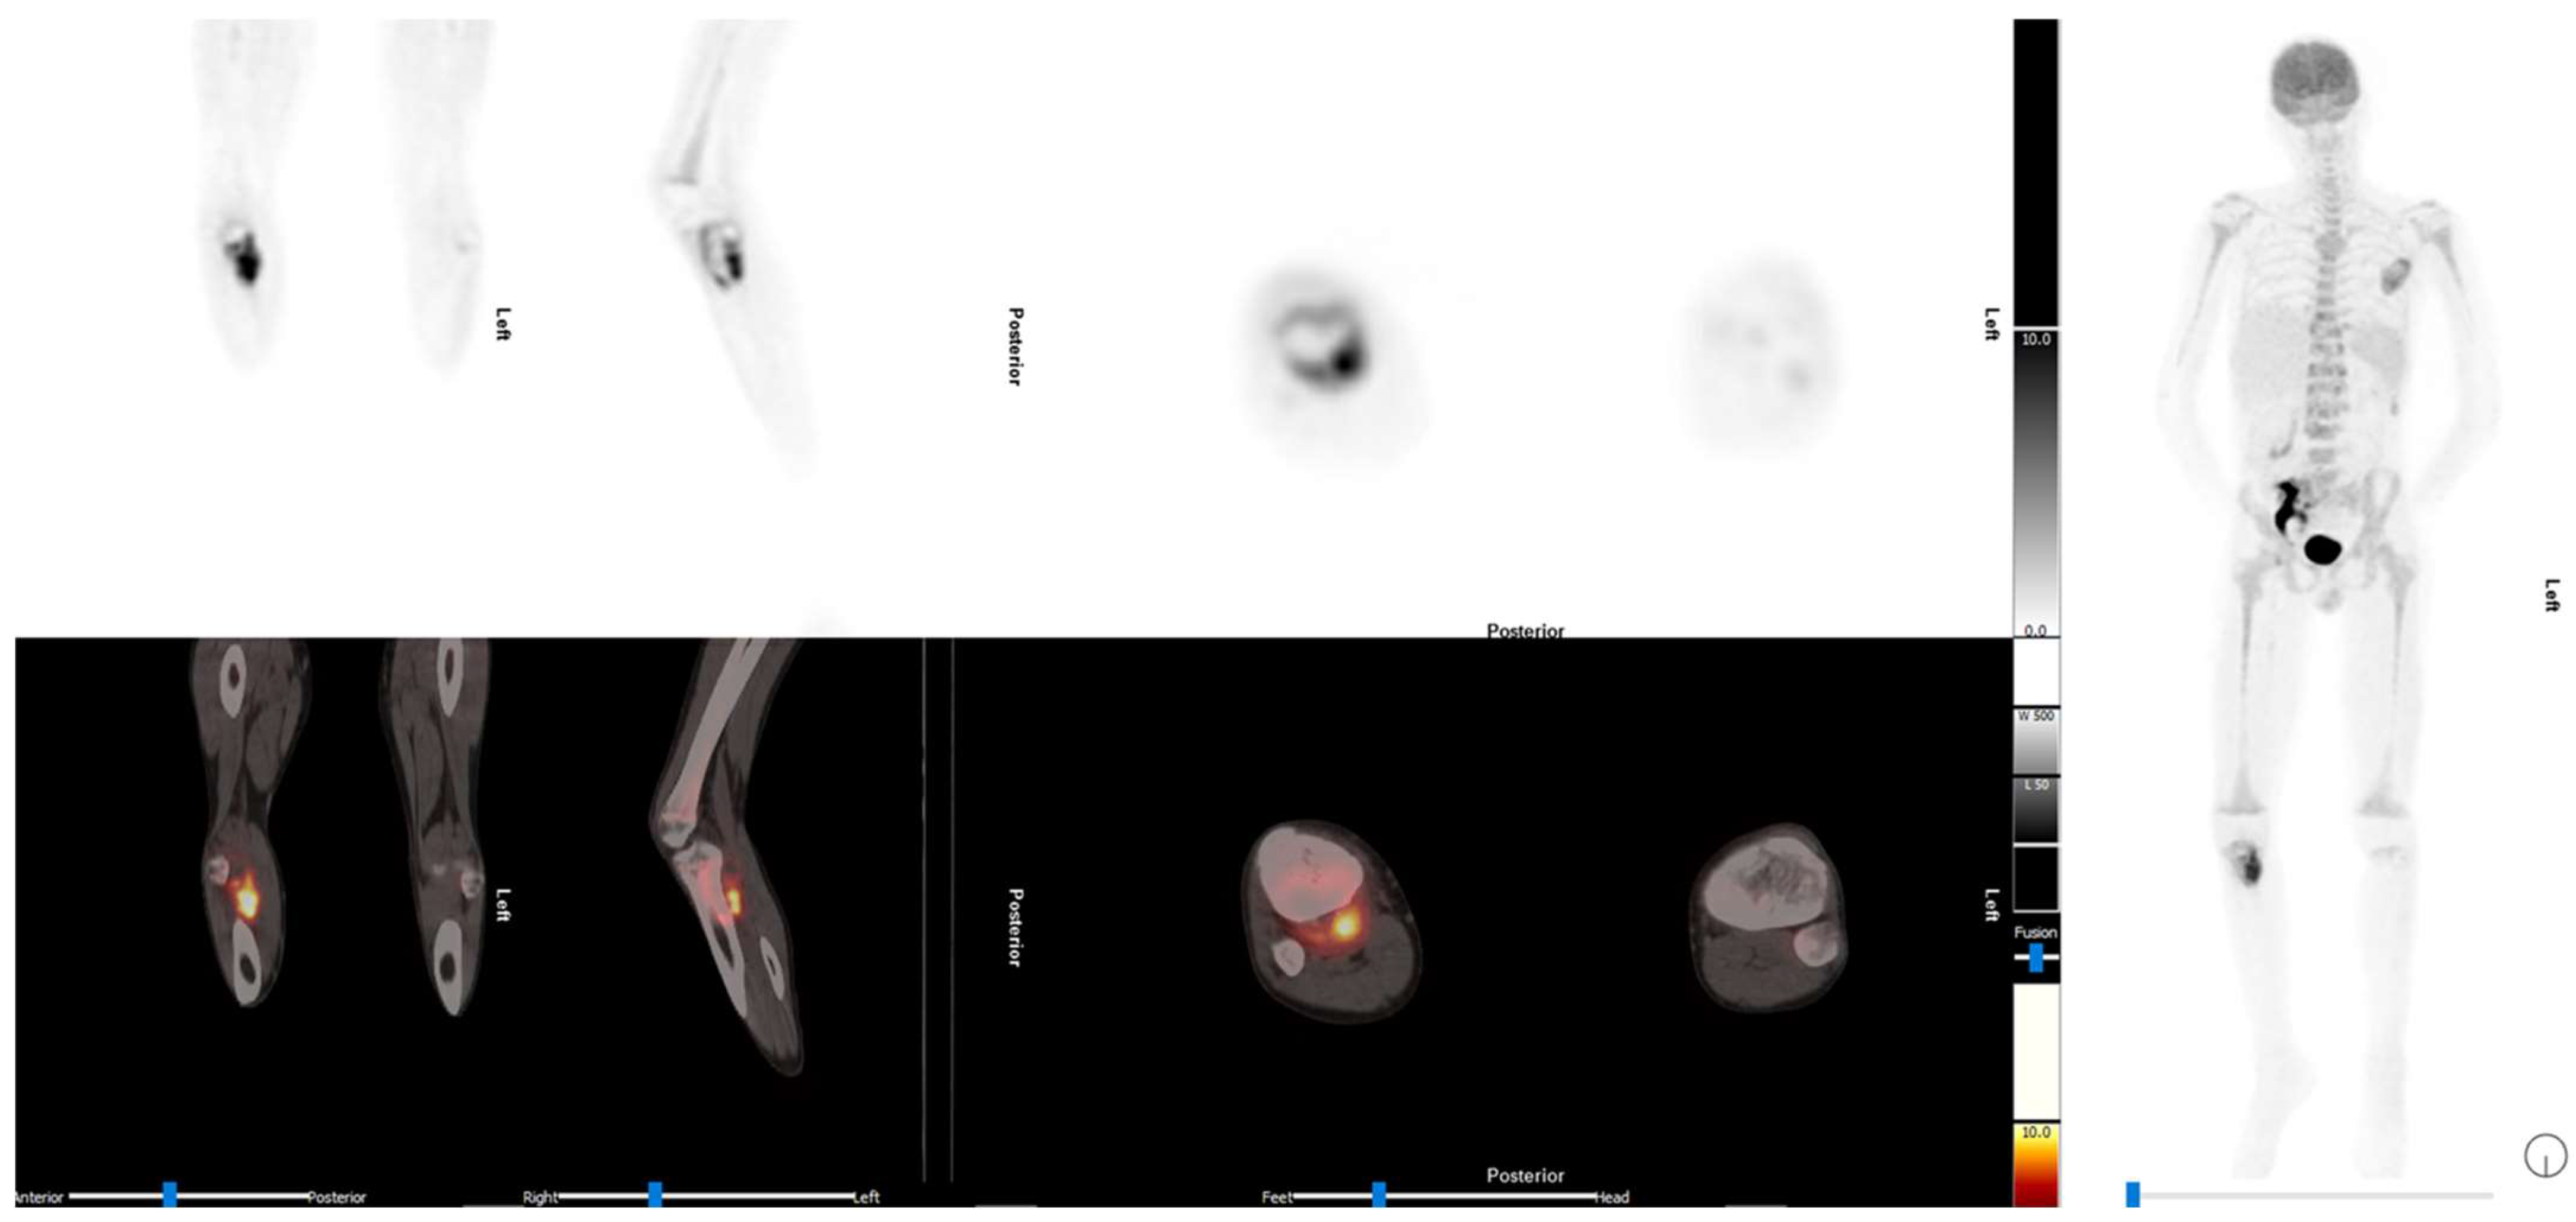

4. Sarcoma

4.1. Osteosarcoma

4.2. Ewing Sarcoma

4.3. Rhabdomyosarcoma